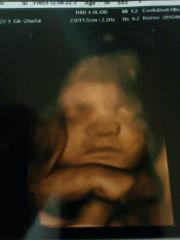

Kép

NEm a legjobb minőség, de ő az én kicsi fiam :)